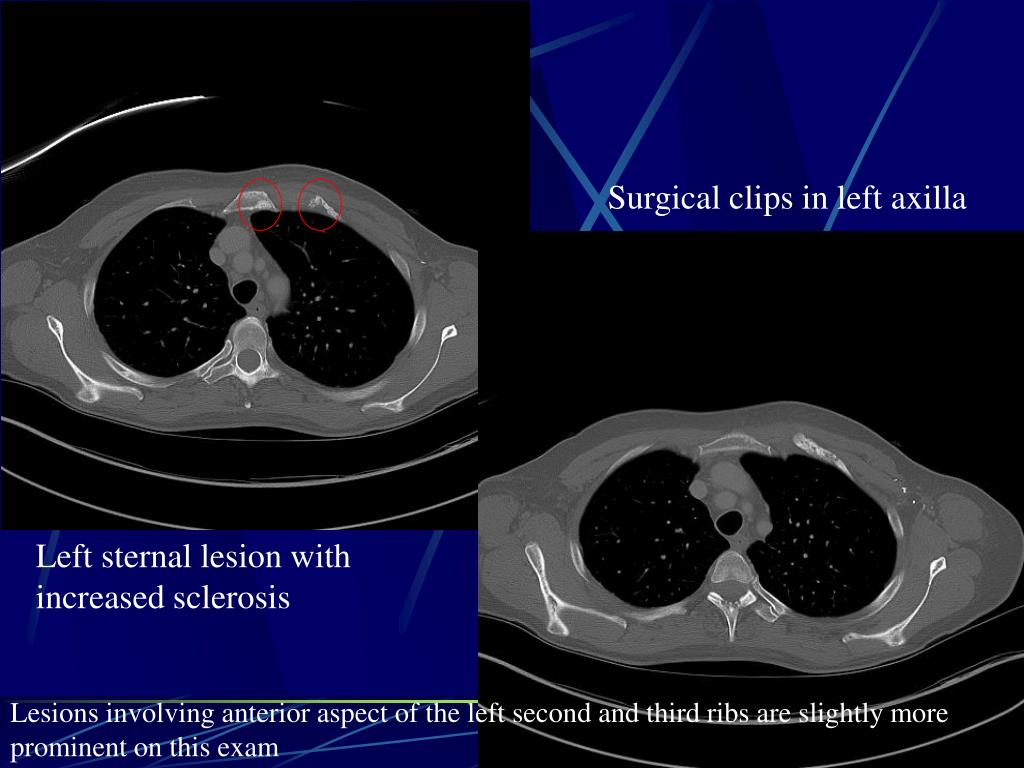

5. Surgical clips in left axilla Left sternal lesion with increased sclerosis Lesions involving anterior aspect of the left second and third ribs are slightly more prominent on this exam